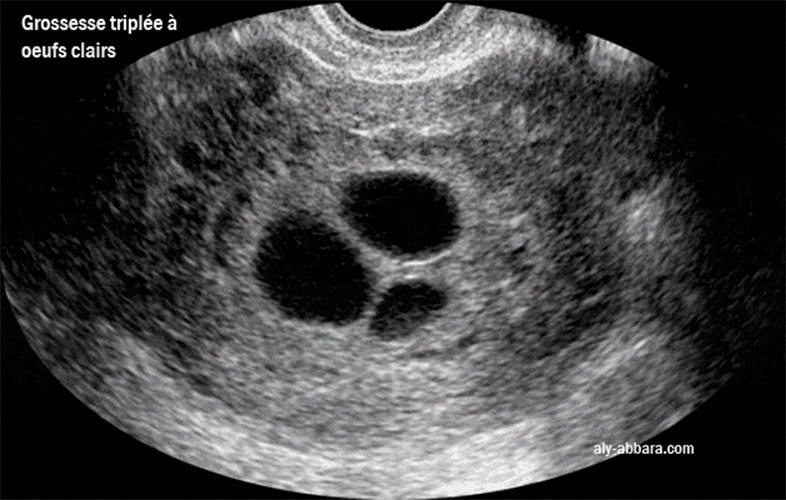

Une coupe échographique transversale d'un utérus gravide, on observe la présence de trois sacs

gestationnels intra-utérins de 24, 22 et 16 mm de grands axes, sans structure

embryonnaire

identifiable. Il s'agit d'un œuf clair multiple (triple) formé de trois ufs clairs.